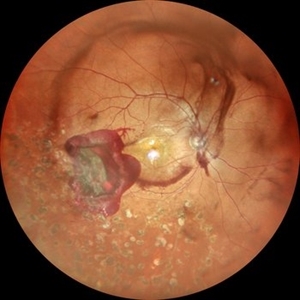

TRACTIONAL RETINAL DETACHMENT IN A CASE OF VASCULITIS

MONTAGE OF A 27 YEAR OLD MALE WITH TREACTIONAL RETINAL DETACHMENT IN A CASE OF VASCULITIS

Photographer: Dr. Akansha Sharma-Retina Foundation, Ahmedabad

Condition/keywords: pan-retinal photocoagulation (PRP), tractional retinal detachment, VASCULITIS